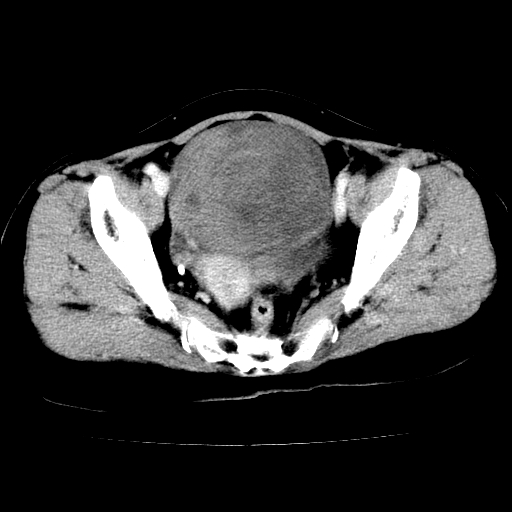

标题: CT24785:女,62岁,发现下腹部肿物半年。 [打印本页]

女,62岁,发现下腹部肿物半年,下腹部不适。

老年女性患者,盆腔囊实性占位,ct增强不均匀强化,未见壁结节,未见腹水及盆腔积液,考虑附件囊腺瘤可能性大!